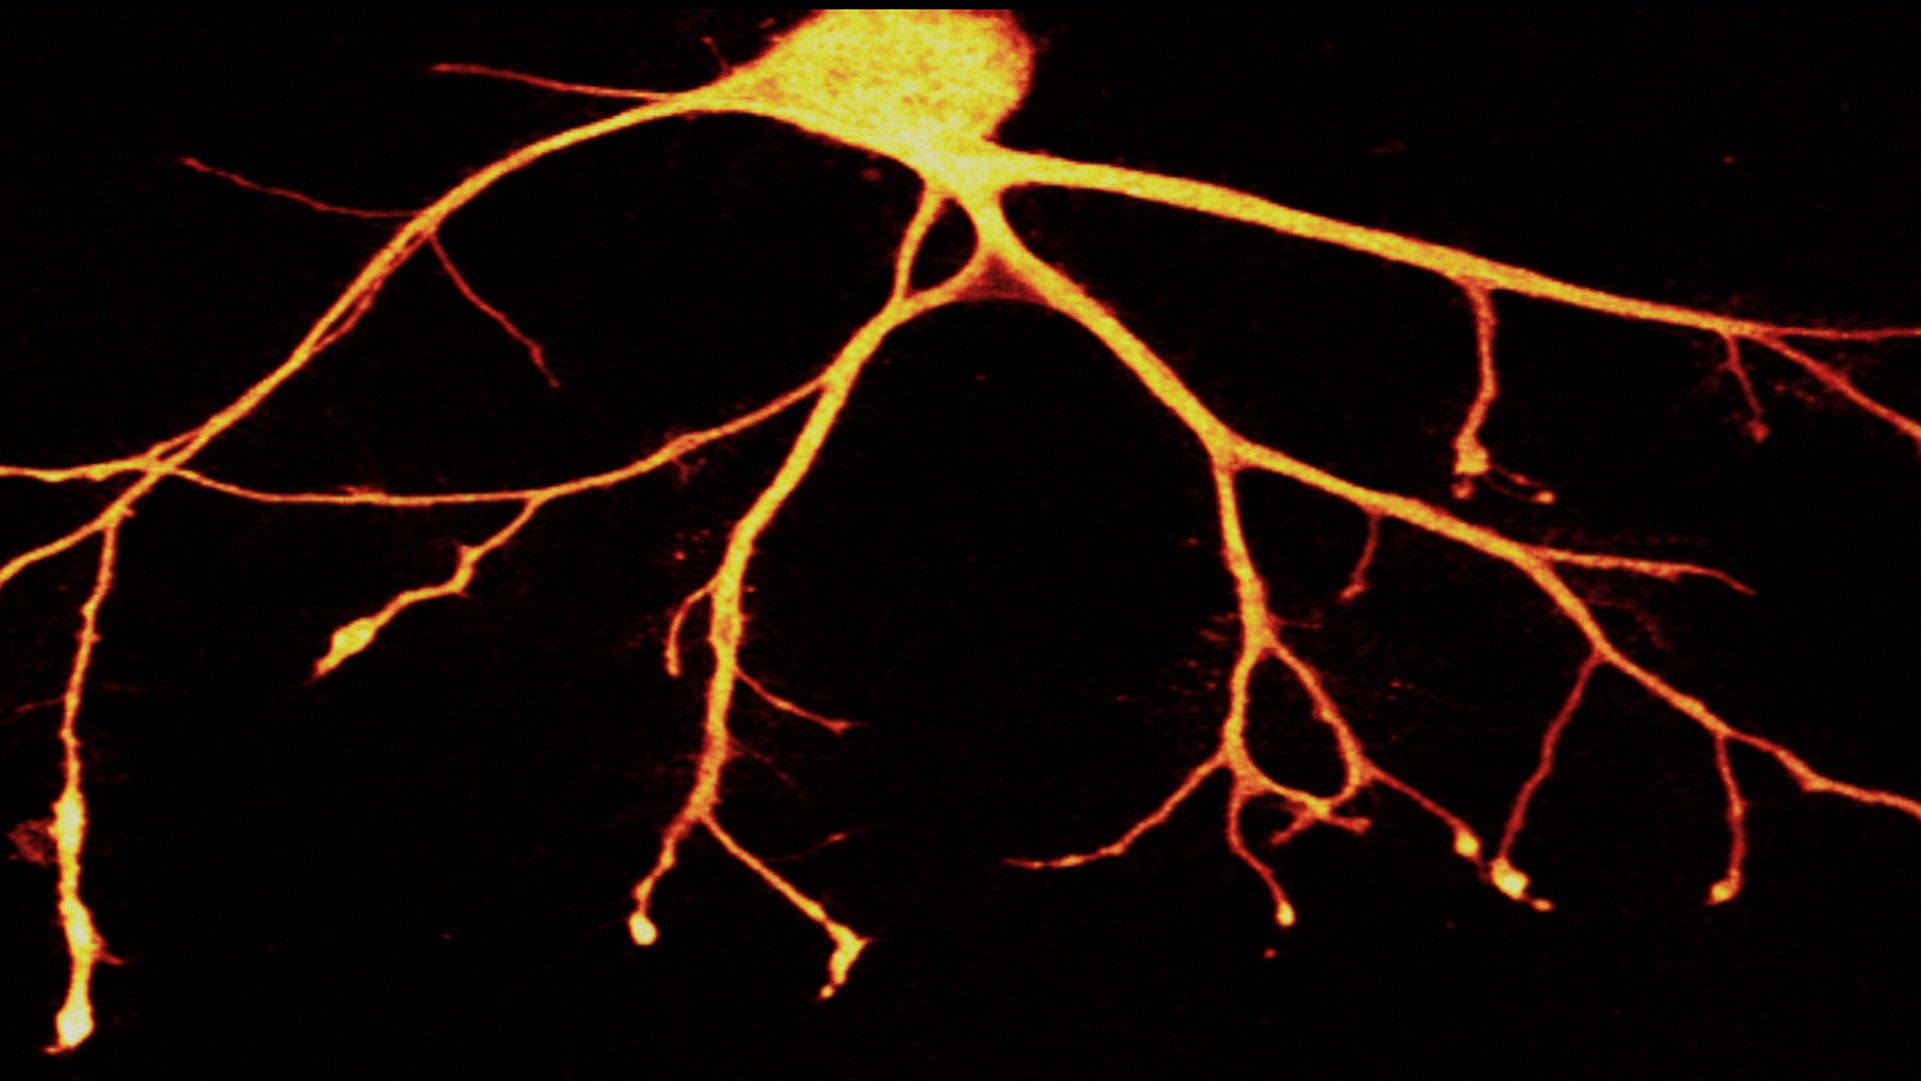

"In Search of Memory" is a very personal portrait of Eric Kandel, the "rock star" of neuroscience and the most important brain researcher of the 20th century. A fascinating documentary about the exciting mystery of the brain which arouses a curiosity in life and learning.